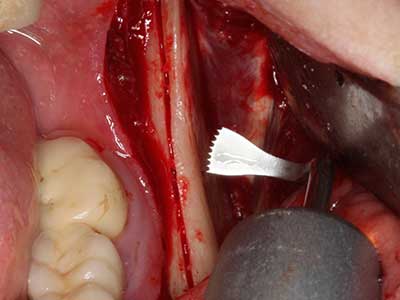

Bone tissue is not simply a mineral structure but also contains a substantial proportion of collagen fibres. This means it not only has good compressive strength but also a degree of flexibility, which can be taken advantage of when performing bone augmentations. In the classical expansion procedure using bone splitting, the atrophied alveolar ridge is split longitudinally and carefully expanded after reaching an adequate osteotomy depth (Fig. 13-16), ideally without substantial removal of the periosteum (Brugnami, Caiazzo et al. 2014, Stricker, Fleiner et al. 2014). Screw and plate systems with increasing expansion distance have proven effective in separating the two bone lamellae while remaining below the fracture threshold. In general, residual bone widths of at least 3–4 mm are required (Chiapasco, Zaniboni et al. 2006) to guarantee adequate flexibility and sufficient bone coverage of the future implants. If necessary, a vertical relief osteotomy on one or both sides can improve flexibility. A combination with additional augmentation techniques, particularly on the buccal side, has been described as an alternative to the classical technique.

The splitting procedure is particularly atraumatic and there is no significant loss of dimension when using piezosaws, and there are no significant differences between implants in split jaws and implants in an alveolar ridge without a bone deficit (Chiapasco, Zaniboni et al. 2006, Danza, Guidi et al. 2009). However, sufficient continuous irrigation is essential, particularly with locally restricted and deep splitting to prevent thermal stress in the apical osteotomy regions.